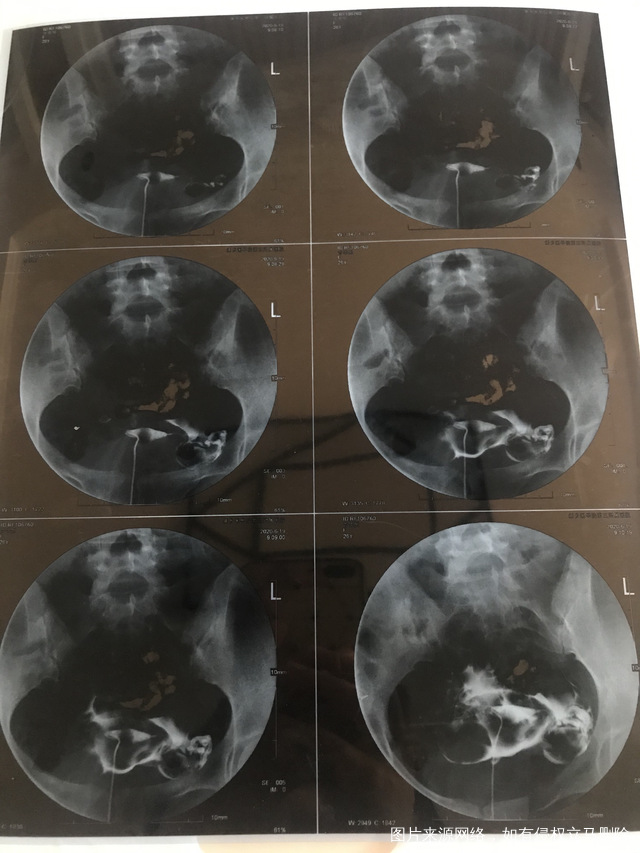

输卵管造影麻烦看一下

输卵管造影,麻烦看一下